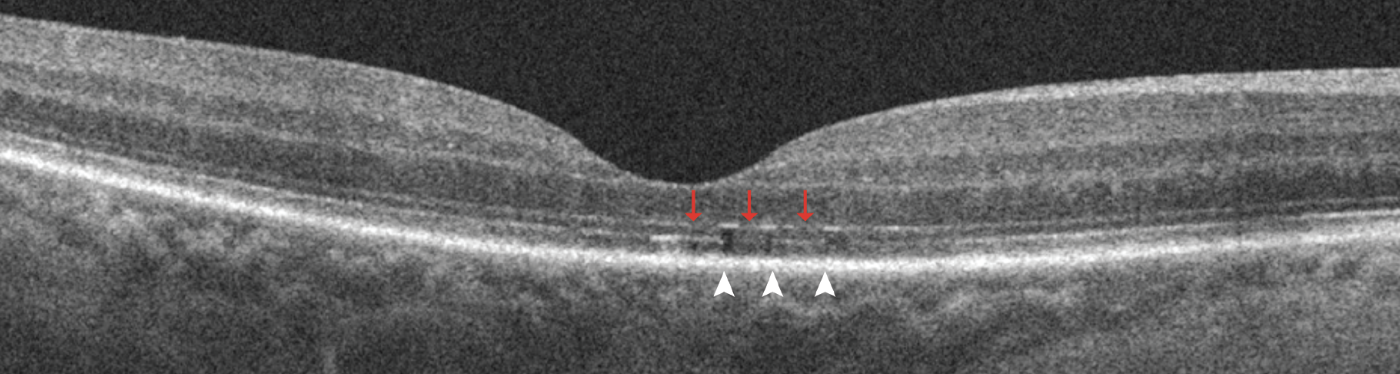

| Figure 1. Representative spectral-domain optical coherence tomography five-line raster images with discontinuity of the outer retinal bands three months after macula-off detachment repair. It shows discontinuity of the external limiting membrane (red arrows) and discontinuity of ellipsoid zone and interdigitation zone (white arrowheads) in the foveal scan. |

Several studies have used OCT to evaluate changes in the outer retina bands after RRD repair and have demonstrated the association of microstructural abnormalities with suboptimal functional outcomes.4,14,16,17 The microstructural imaging analysis of the fovea involved assessing for discontinuity of the outer retinal bands, specifically the external limiting membrane, ellipsoid zone and the interdigitation zone (IZ) (Figure 1, above), and the presence of outer retinal folds (ORFs) (Figure 2, below).